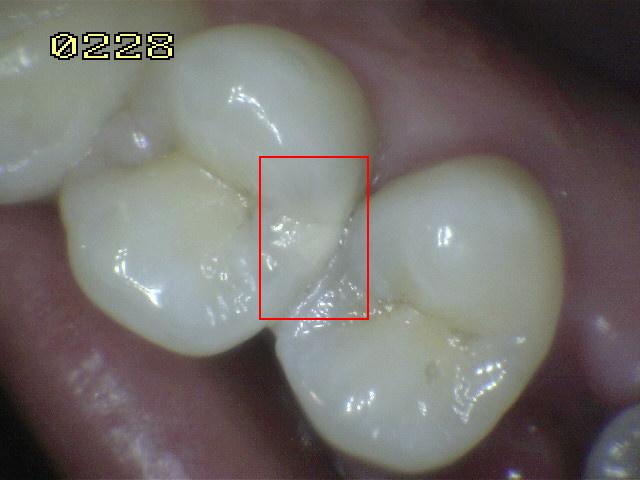

Código 4

(Caries Moderada): Sombra oscura

de dentina subyacente al esmalte intacto con o sin interrupción

localizada del esmalte

-

Esta lesión aparece como una sombra de decoloración

visible a través de una superficie de esmalte intacta, la que puede o no mostrar signos

de descomposición localizada del esmalte, como la microcavidad y /o discontinuida

< 0,5mm. después del secado con aire durante 5

segundos

La aparición de

la sombra se ve a menudo con más facilidad cuando

el diente está húmedo. El área oscura es una

sombra intrínseca que puede aparecer gris, negro-azul o

marrón-anaranjado,

a través de las paredes del esmalte vestibular, lingual o

palatino